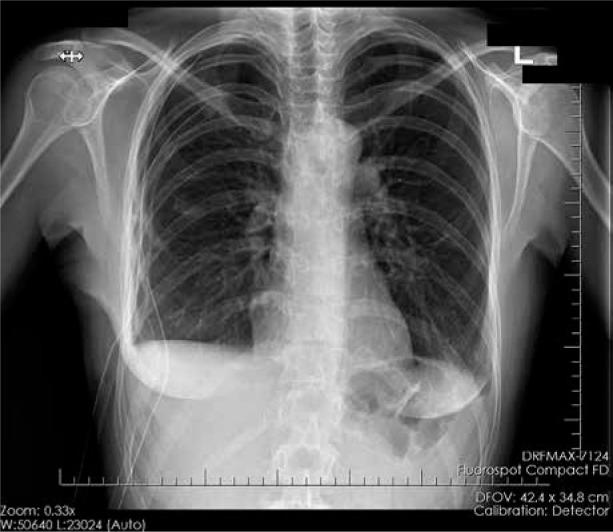

Catamenial pneumothorax (CP) is an uncommon disease related to thoracic endometriosis or diaphragmatic perforation. It is defined as an occurrence of spontaneous pneumothorax around the time of menstruation in the population of women of reproductive age with no other lung diseases. Catamenial pneumothorax is often misdiagnosed and classified as a spontaneous pneumothorax, and no in-depth gynaecological diagnostic is performed. Here we present 3 cases of female patients admitted to the Department of Thoracic Surgery with the aim of surgical treatment of recurrent CP. In all 3 cases, a temporal association between pneumothorax and menstruation was identified. In 2 presented cases the patients were diagnosed with endometriosis and other gynaecological diseases. The previous incidents of CP were treated conservatively, with suction drainage of the pleural cavity or with thoracocentesis, but the treatment did not prevent relapses. In the Department of Thoracic Surgery, each patient was operated on with the use of video-assisted thoracoscopic surgery, which is considered to be a good therapeutic option. In the case of 2 patients the surgery eliminated the relapses, 1 patient required radical lung decortication. The literature on the subject indicates the potential benefits of hormonal treatment of CP. It is suggested that using such pharmacological treatment may reduce the risk of relapse after surgery.

月经性气胸(CP)是一种与胸段子宫内膜异位症或膈肌穿孔相关的罕见疾病。它被定义为在无其他肺部疾病的育龄女性人群中,在月经期间发生的自发性气胸。月经性气胸常被误诊并归类为自发性气胸,且未进行深入的妇科诊断。在此,我们介绍3例因复发性CP而入住胸外科接受手术治疗的女性患者。在所有3例病例中,均发现气胸与月经之间存在时间关联。在2例病例中,患者被诊断出患有子宫内膜异位症和其他妇科疾病。既往CP发作时采用胸腔闭式引流或胸腔穿刺进行保守治疗,但治疗未能预防复发。在胸外科,每位患者均接受了电视辅助胸腔镜手术,该手术被认为是一种良好的治疗选择。在2例患者中,手术消除了复发,1例患者需要进行根治性肺剥脱术。关于该主题的文献表明,CP的激素治疗具有潜在益处。建议使用此类药物治疗可能会降低术后复发风险。